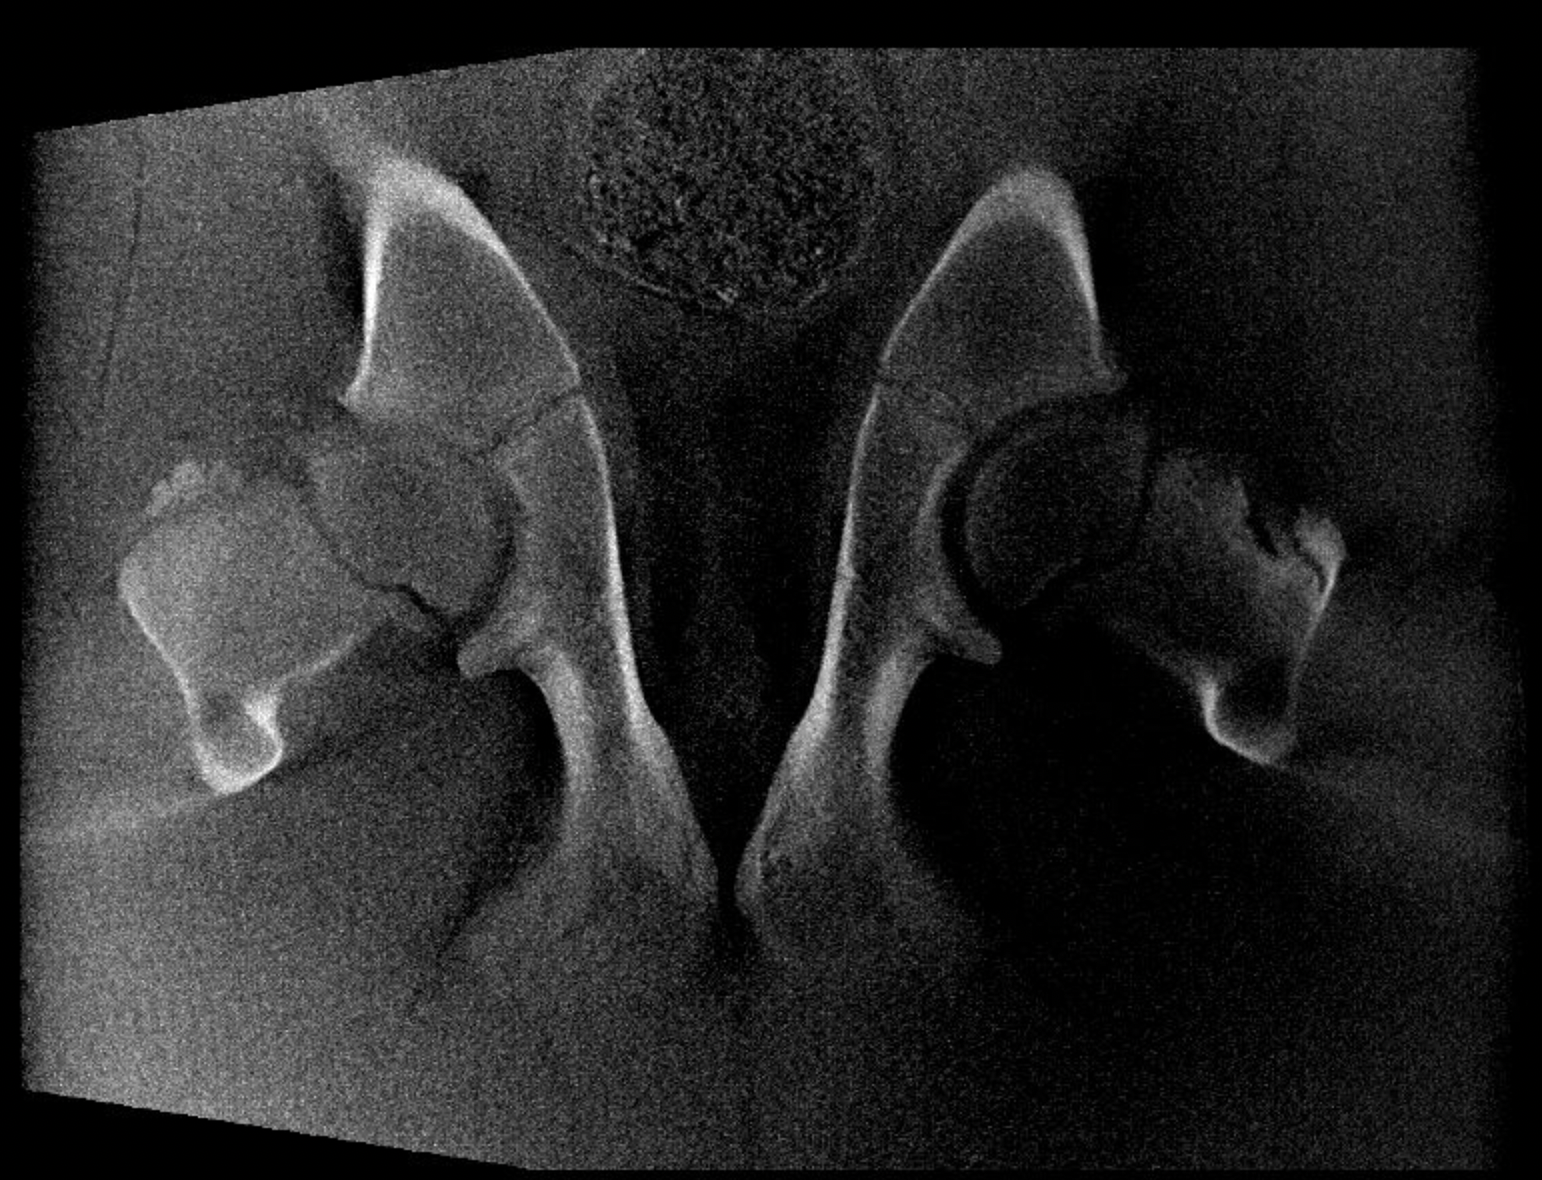

Our High Definition Volumetric Imaging (HDVI) technology represents the most advanced stage of Flat Panel CT technology. It offers exceptional diagnostic imaging for both hard and soft tissues, in diagnostic settings and intraoperative theaters. It is the gold standard for orthopedic applications.

Scan of the head, neck and limbs in standing position

Diagnostic and intraoperative use

Diagnostics, preoperative, intraoperative and post-operative environments: our technology offers full capabilities.

Scan of the standing horse

Pegaso scans head, neck and limbs of the standing horse